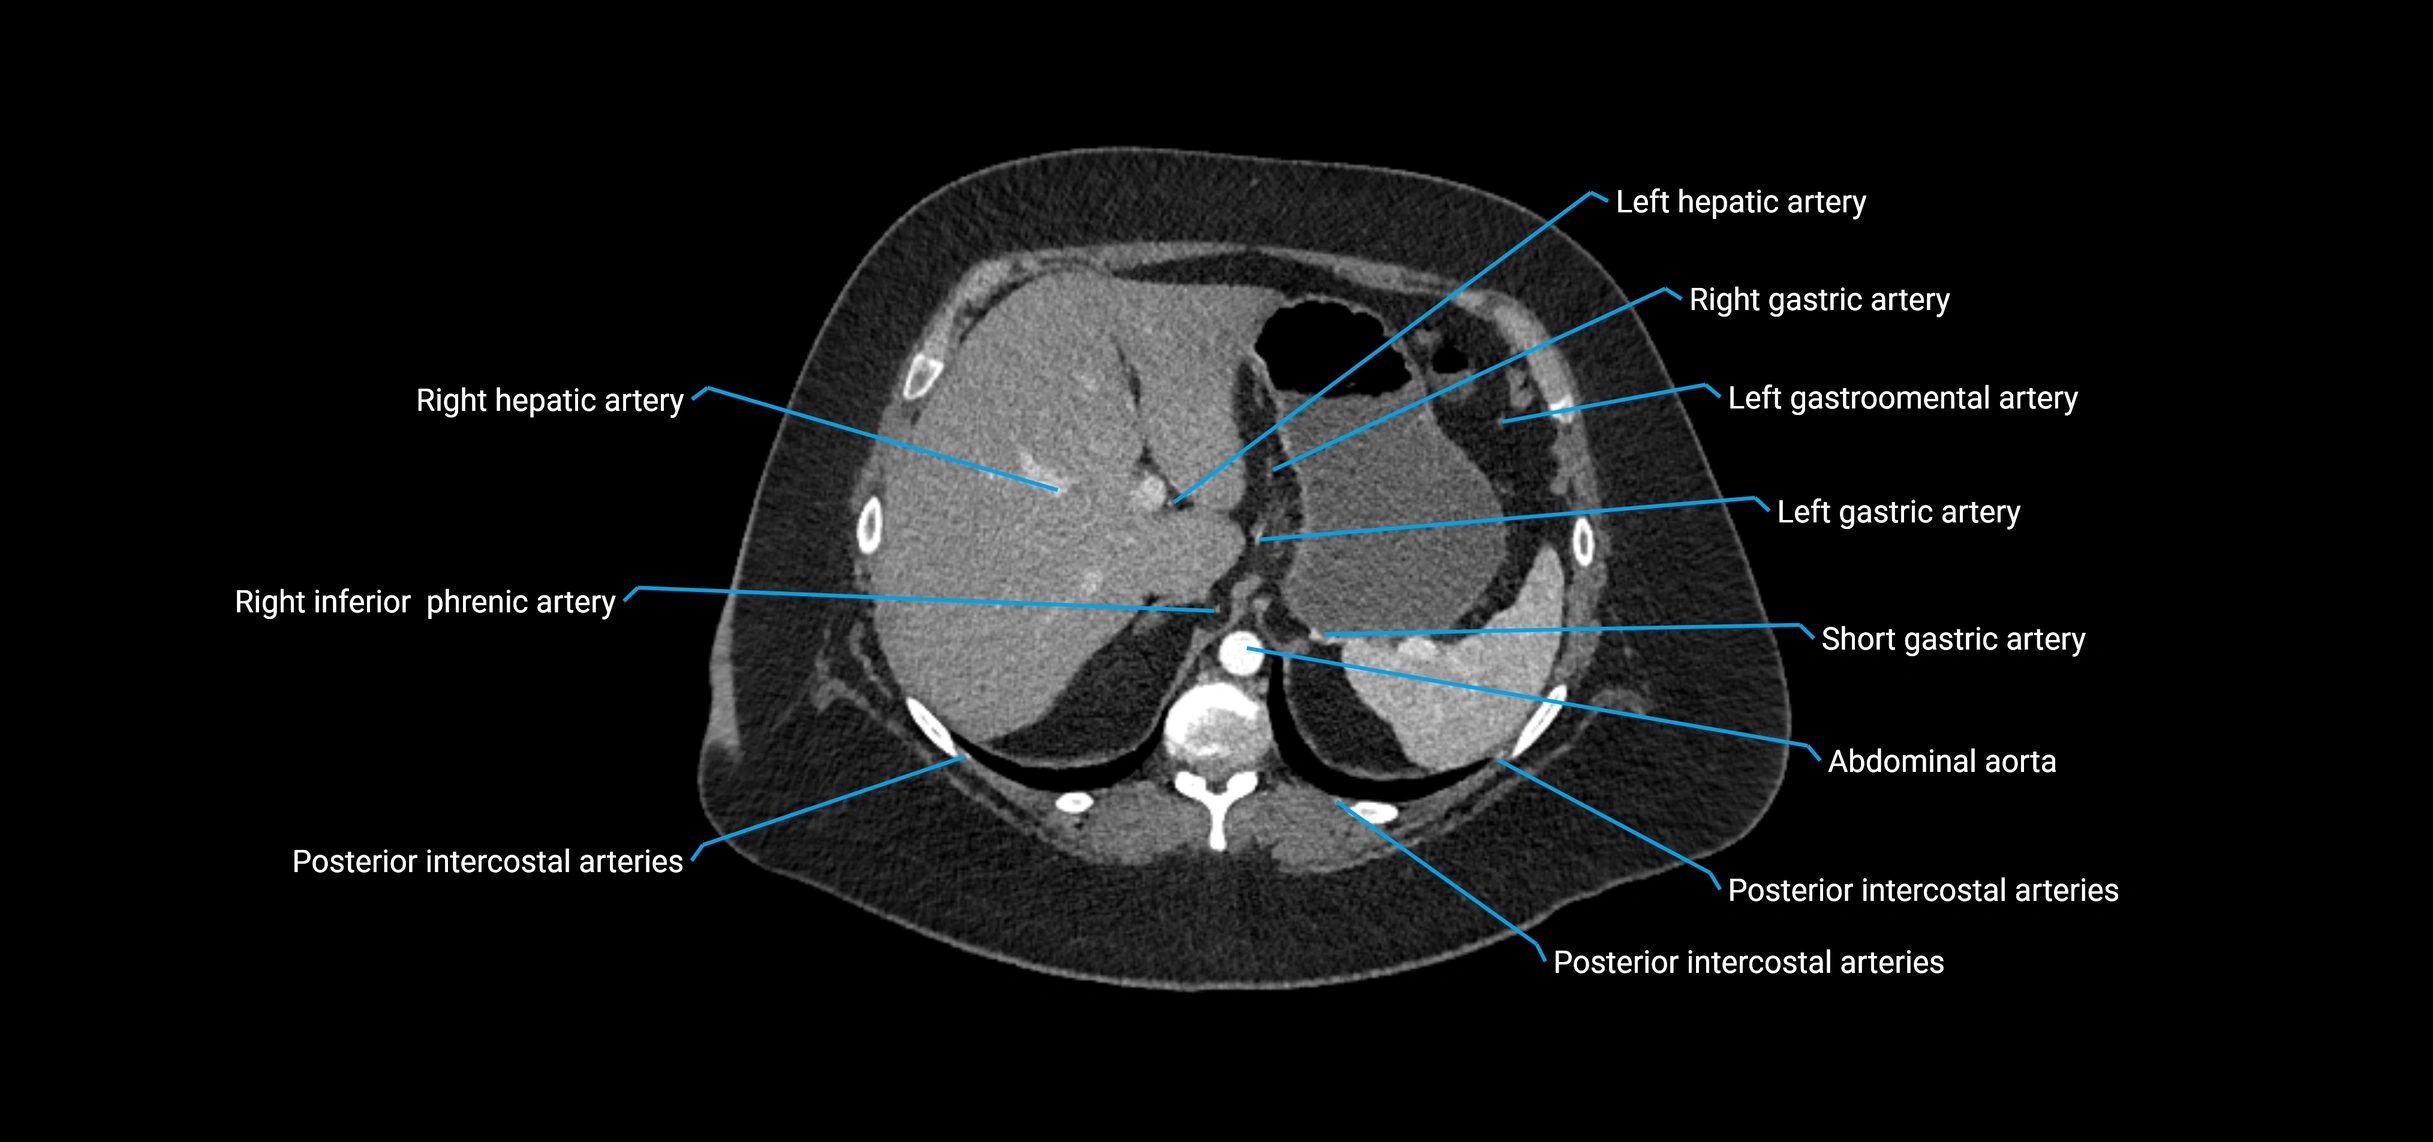

Contrast-enhanced CT (CTA):

• Gold standard for abdominal aortic imaging

• Provides excellent detail of lumen, wall, aneurysm, thrombus, and branch vessels

• Multiplanar and 3D reconstructions help in aneurysm measurement, stent graft planning, and dissection evaluation